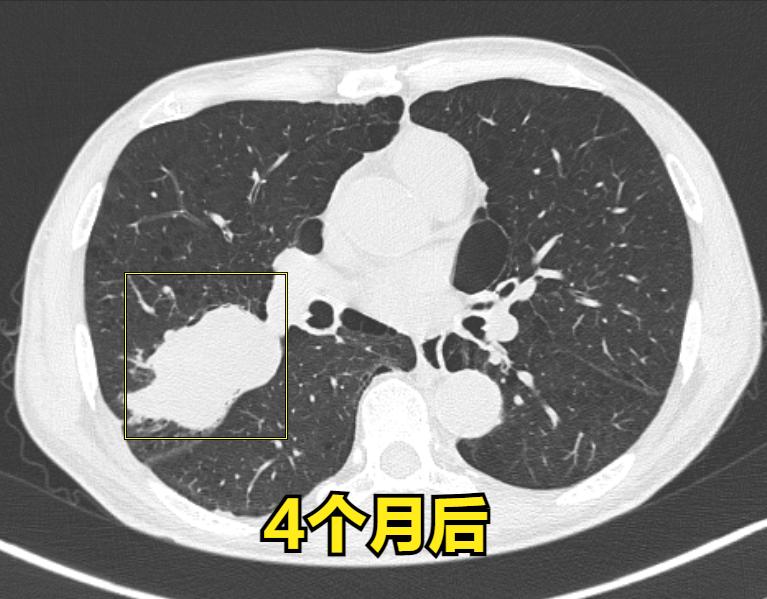

发现病灶4个月,因为惧怕未行活检,恐失去手术机会。

73岁 男性 患者于4个月前发现右肺出现占位性病变。当时他住院在一家顶级医院接受治疗,但病灶的大小并不小。之前我也阅片提示恶性的,尽管都住院期治疗了,医生也建议进行活检以明确诊断,但患者拒绝了。因此,他的病情没有得到明确的解决,最后他选择回家观察。4个月后,他再次找到我进行检查,发现病灶比之前明显增大,同时出现了恶性征象,我们开始考虑是否为肺癌。最终,病理检查结果也证实了肺癌

这位朋友特别遗憾,和家属之前进行了长时间的沟通,但在4个月前他们不愿意进行进一步的检查。由于病灶的恶性程度较高,4个月后病情明显恶化,胸膜也受到了累及,这可能导致失去直接手术的机会。如果在4个月前进行了肺叶切除手术,康复的可能性会更高。